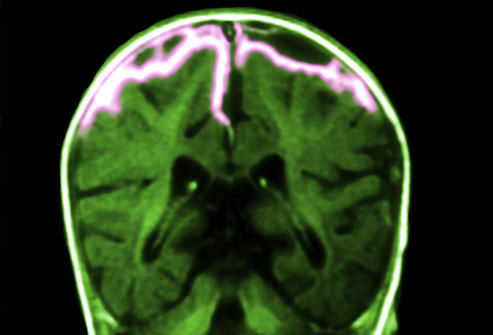

Viêm màng não

![]() |

Viêm màng não là tình trạng viêm hoặc nhiễm trùng ở mô xung quanh não và tủy sống. Ở trẻ vị thành niên và người lớn, triệu chứng chính là đau đầu, sốt và cứng gáy.

Trẻ nhỏ có thể bị những triệu chứng giống cúm hoặc cực kỳ kích động. viêm màng não do vi rút thường nhẹ, nhưng viêm màng não do vi khuẩn thì nặng hơn với những hậu quả nghiêm trọng nếu không được điều trị nhanh chóng. Hiện đã có vắc xin để phòng ngừa một số vi khuẩn gây viêm màng não.